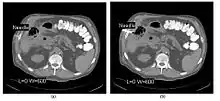

CT Fluoroscopy

- CT Fluoroscopy (CTF) has also been referred to as Continuous CT or Real-Time CT since it involves generating tomographic images at sufficiently high frame rates to allow guidance of needle placement in small or deep-seated lesions. Applications can include biopsy of thoracic lesions, biopsy/drainage of pelvic lesions, vertebroplasty and drainage/aspiration of intracranial haematomas. The advantages of CTF include increased target accuracy and reduced procedure times[45].

- The major difference to a conventional CT system is that high speed reconstruction techniques are applied, and that an operator panel, exposure footswitch and image monitor are installed in the scanning room for use by the interventionist. Controls are generally available for table movement, gantry tilt, laser grid definition and fluoroscopic factors. The other significant operational change relates to the choice of tube current which is typically 30-50 mA in CTF. This should be compared with typical screening currents used in conventional fluoroscopy of up to 5 mA, so that CTF can be regarded as a high dose procedure. In this context, additional beam filtration can be introduced automatically for CTF procedures to reduce patient exposure by up to 50%, for example. Furthermore, the use of protective gloves and needle holders can reduce the radiation exposure to the hands of the interventionist.

- The value of N is typically 30o, 45o or 60o, with frame rates of 12, 8 and 6 frames per second, respectively. In the case of 60o updates and 6 frames per second, the delay between each image is 0.17 seconds. A Last-Image-Hold (LIH) technique can be used while the image is being updated with the resulting time lag being considered by the interventionist in terms of biopsy technique. Example images are shown in Figure 7.15.11. The display of three adjacent slices of thickness 5 mm with MDCT scanning can be used to improve visual feedback to the interventionist as the needle progresses. In addition, multi-planar reconstructions (MPR) and volume rendered 3D images can be used to enhance fine control.